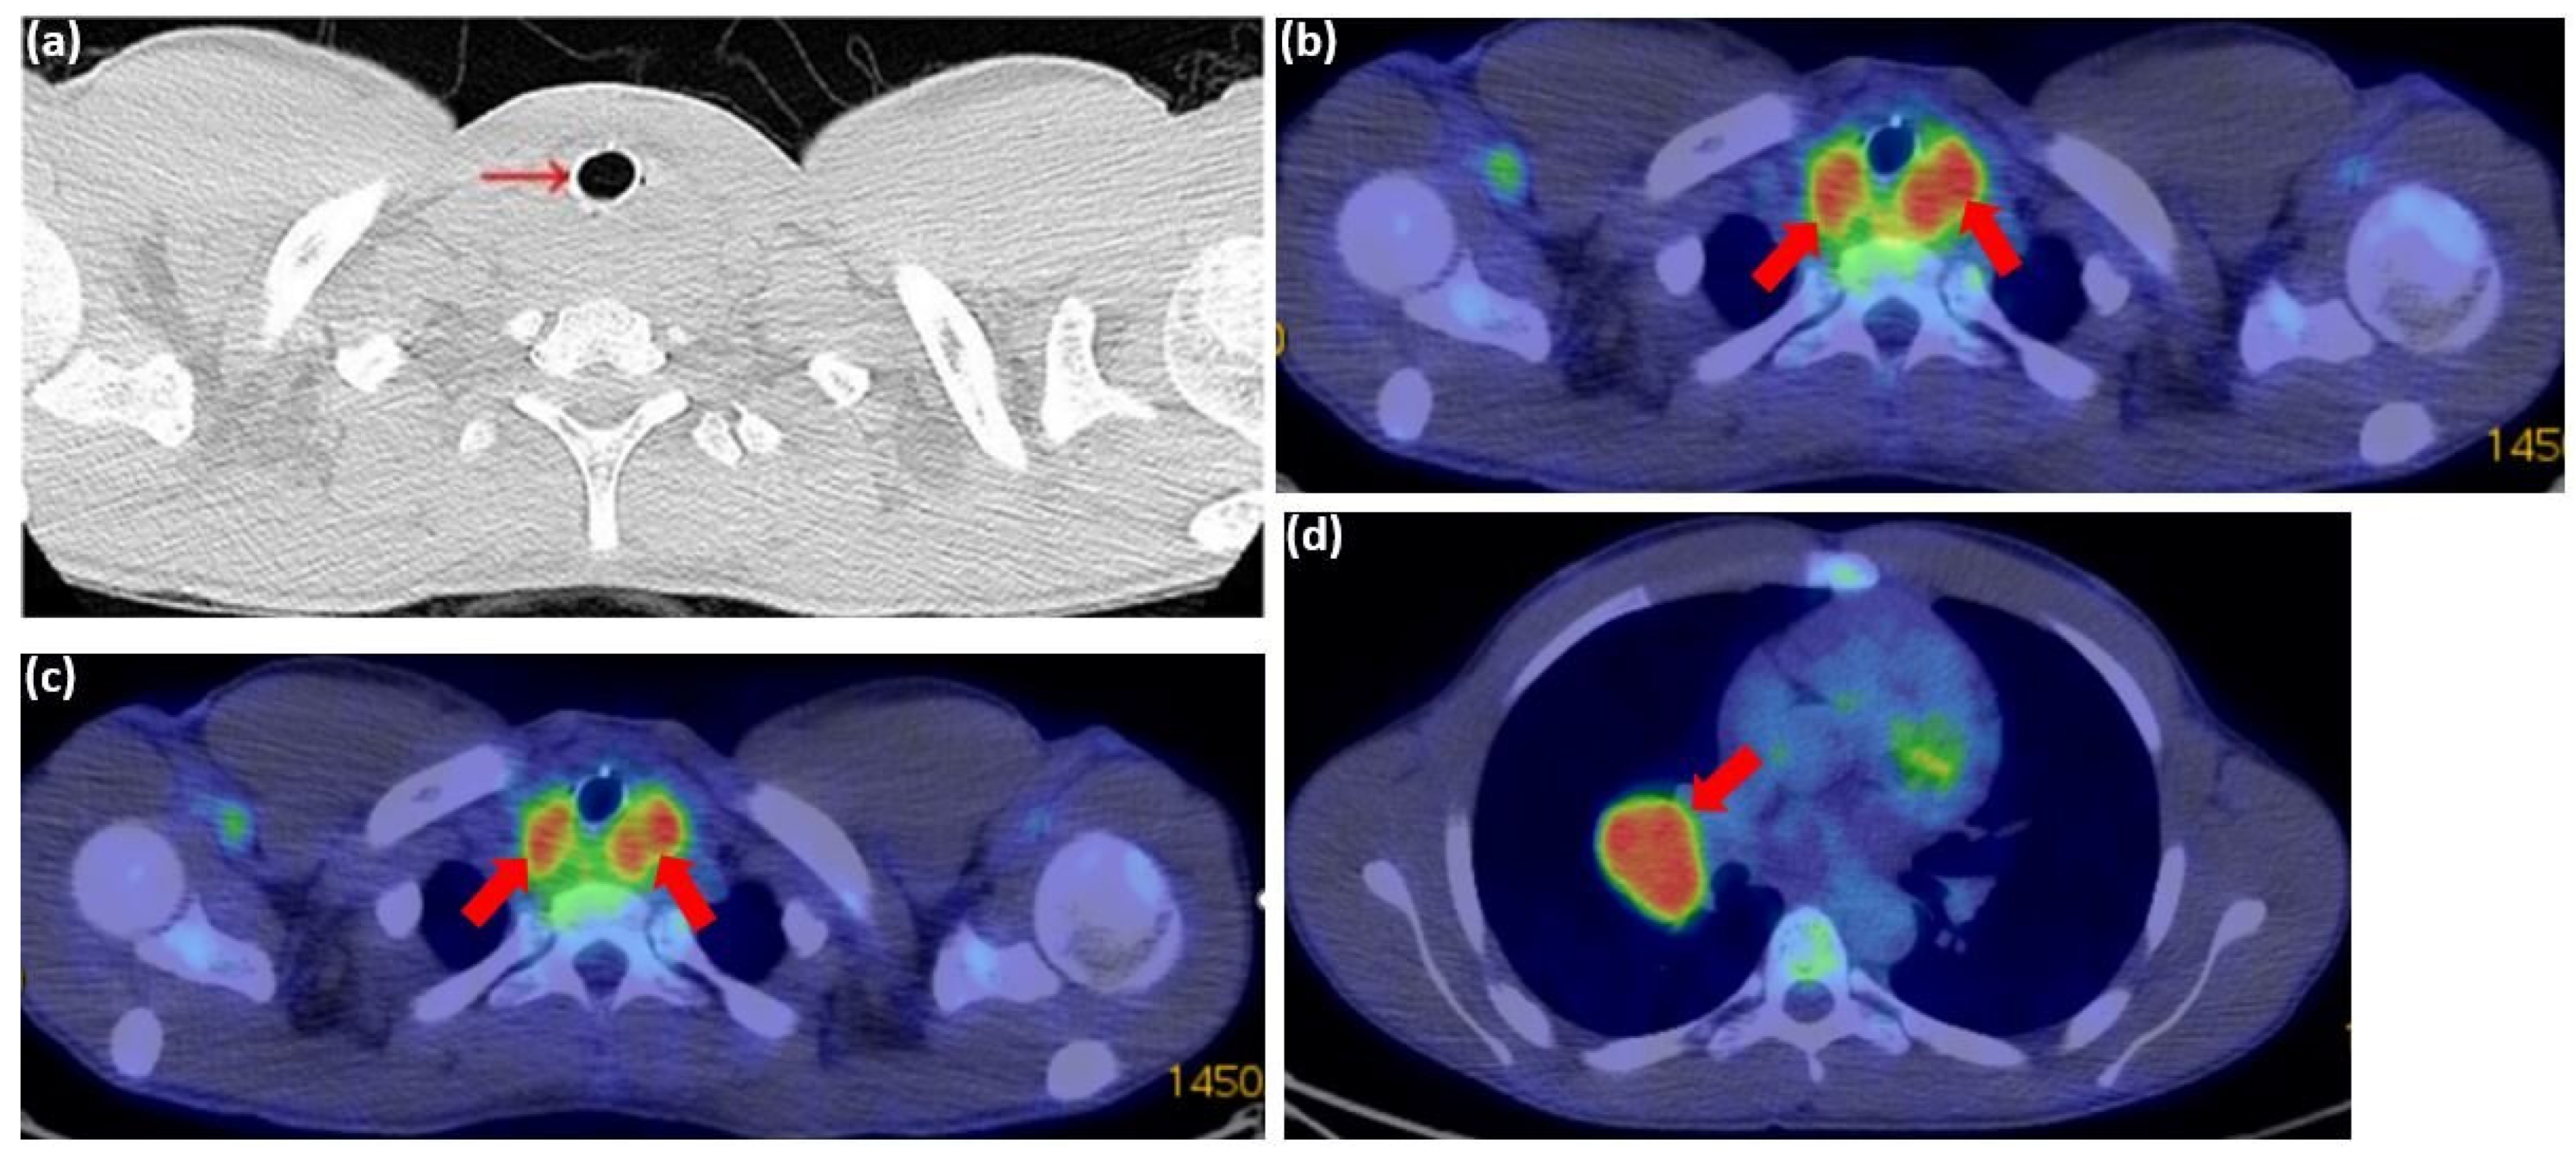

2. Case Report